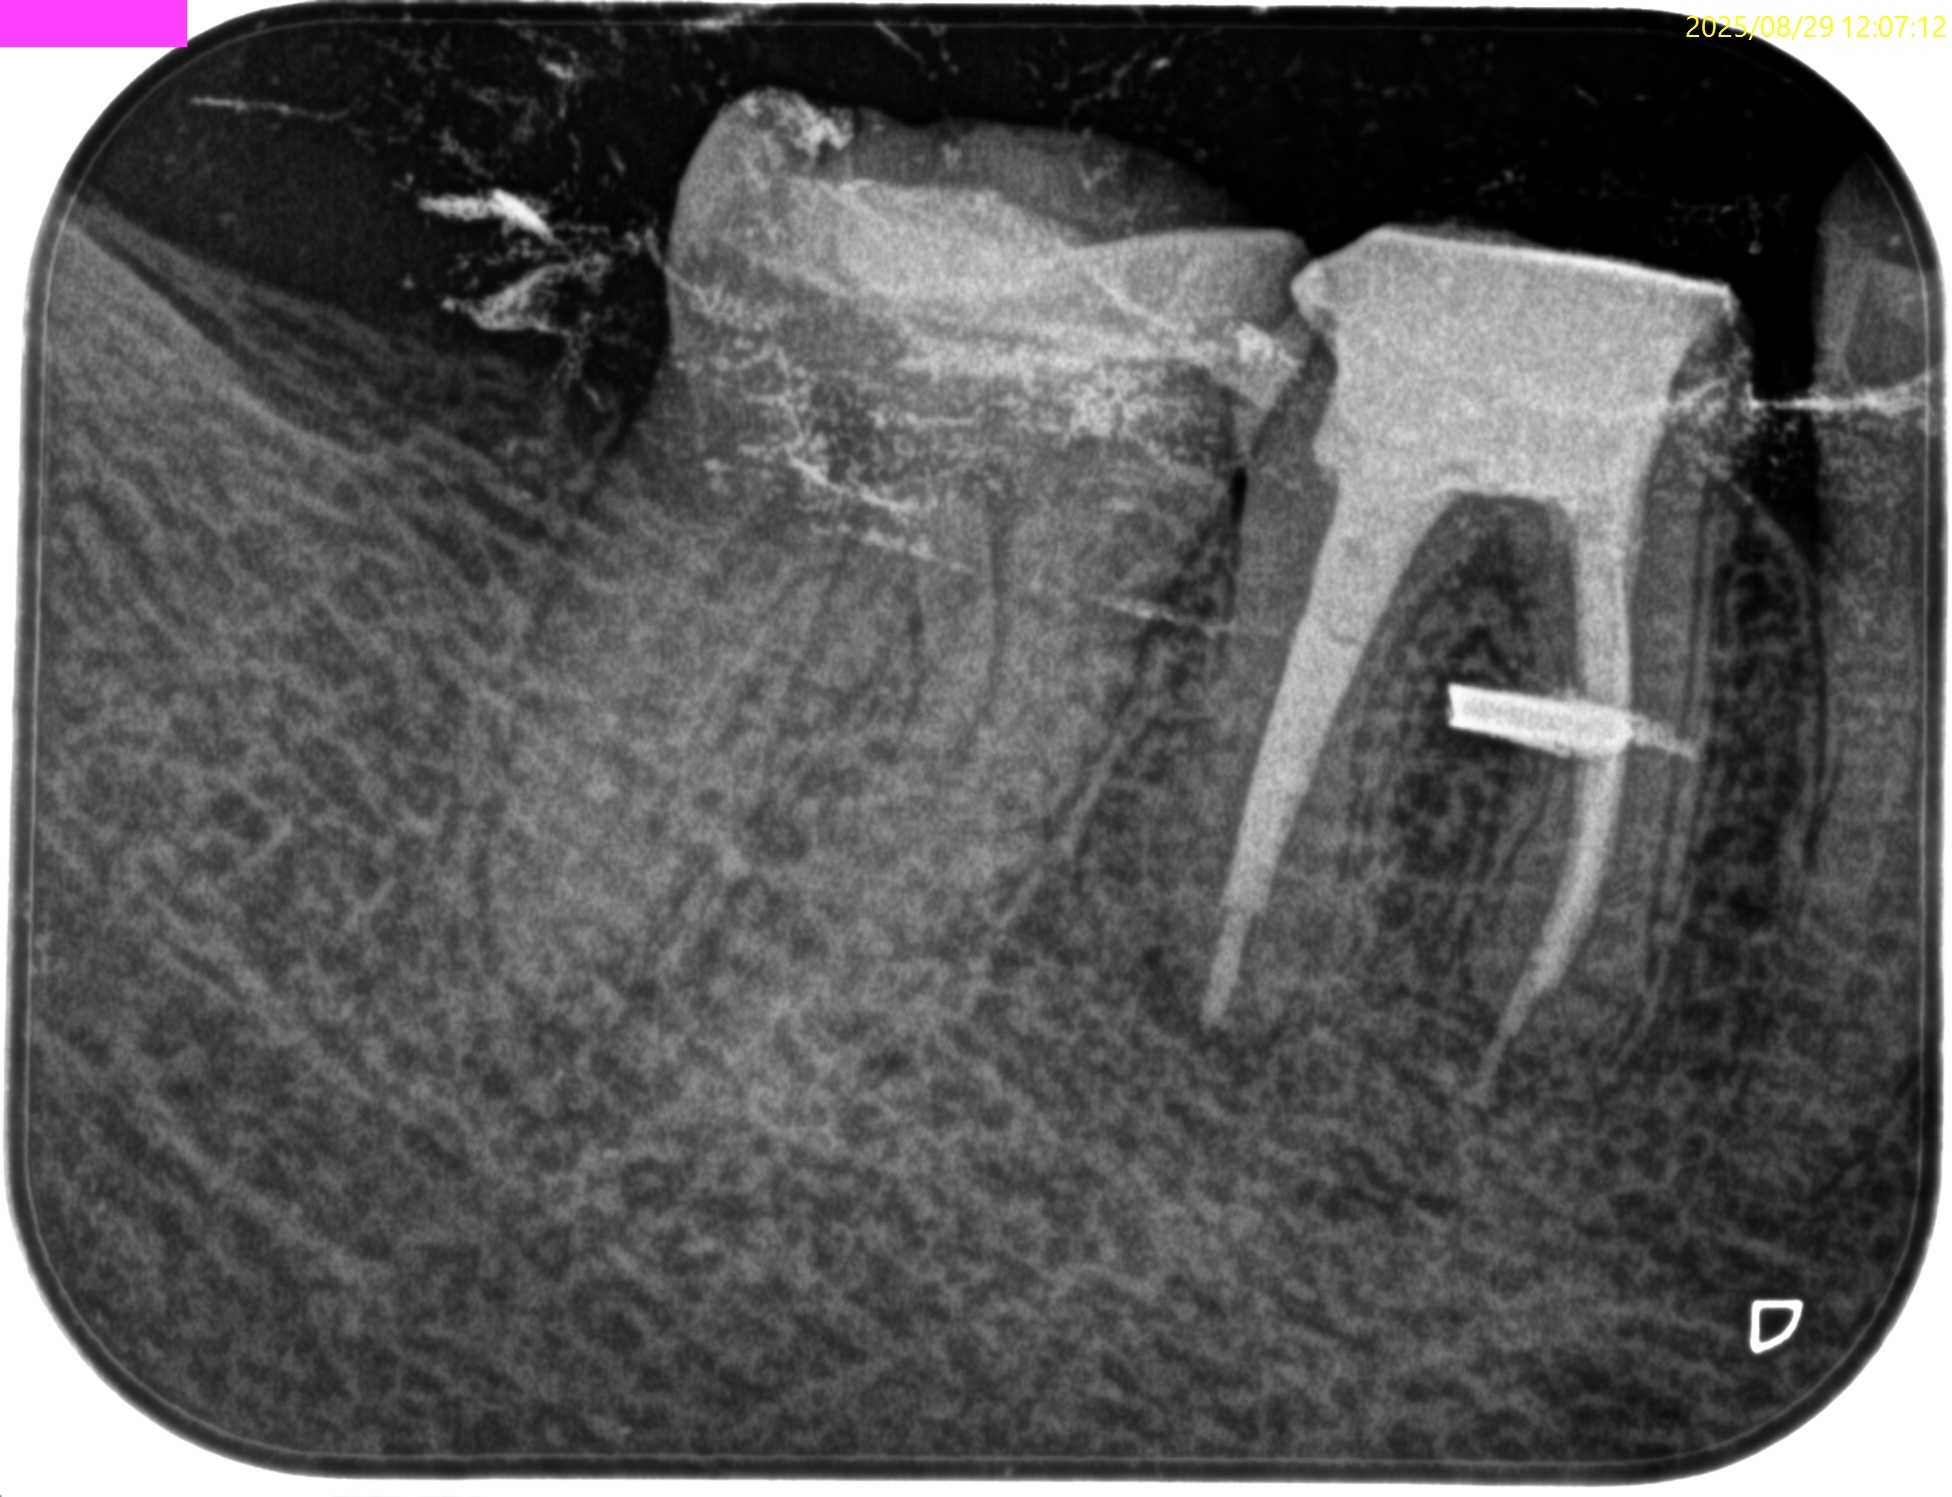

術後にPA, CBCTを撮影した。

MB

ML

D